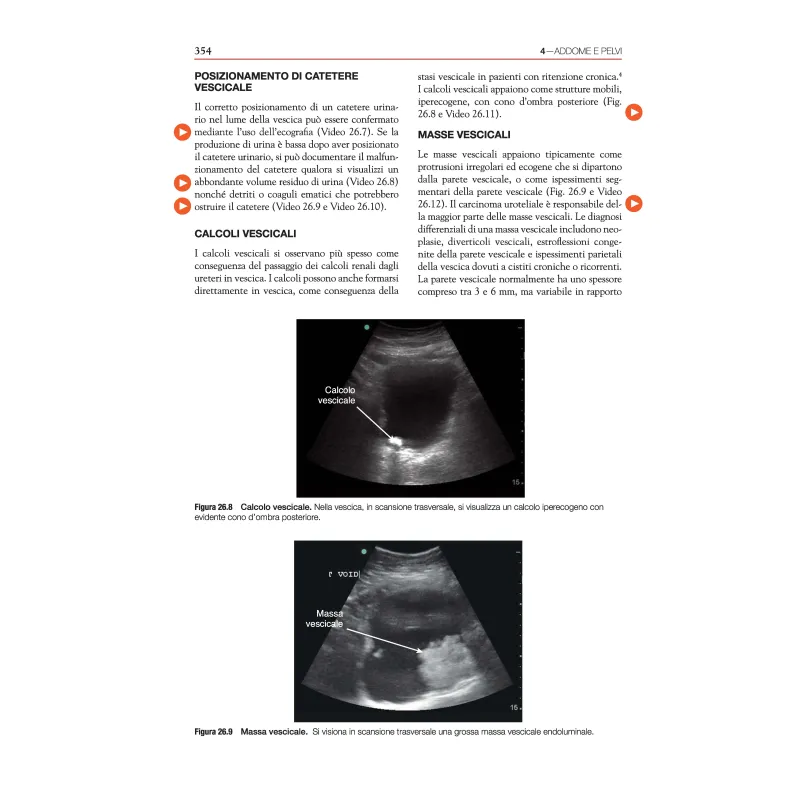

È stato dimostrato che l’ecografia point-of-care (POCUS) rende le procedure più sicure, accelera e aumenta l’accuratezza delle diagnosi e incrementa la sicurezza nel processo decisionale clinico. La POCUS è una delle poche nuove tecnologie che avvicina l’operatore sanitario direttamente al letto del paziente, migliorando così l’esperienza sia dei pazienti che degli operatori sanitari stessi. La prima edizione di Point-of-Care Ultrasound è stata pubblicata nel 2014 e ha posto le basi per la condivisione delle conoscenze tra diversi ambiti specialistici che utilizzano le più diverse applicazioni ecografiche al letto del paziente. Dalla sua prima pubblicazione, il libro è stato tradotto in cinese e spagnolo, con migliaia di copie distribuite in tutto il mondo. Man mano che gli operatori sanitari imparavano a conoscere le potenzialità della POCUS, un numero crescente di essi ha utilizzato questo libro. Data la natura visiva e dinamica dell’ecografia, questo libro mette a disposizione numerosi video. Il suo stile da manuale, i capitoli concisi, le figure esplicative e i suggerimenti di insegnamento pratici sono accattivanti anche per i medici più impegnati che cercano di ampliare le loro conoscenze in materia di ecografia. In questa seconda edizione, abbiamo allargato i contenuti in diversi modi. In primo luogo, abbiamo aggiunto sei nuovi capitoli sull’emodinamica, sull’ecocardiografia transesofagea, sul secondo e terzo trimestre di gravidanza, sulla pediatria, sulla neonatologia e sull’ecografia transcranica. In secondo luogo, abbiamo aumentato i contenuti video online da circa 300 a oltre 1000 video che mostrano gli aspetti ecografici normali e patologici. In terzo luogo, abbiamo aggiunto nuovi casi clinici e domande di verifica alla fine di ogni capitolo, sottolineando i punti chiave dell’apprendimento. Infine, ci siamo tenuti al passo con questo campo in rapida evoluzione aggiornando la letteratura, le immagini e le figure in ogni capitolo. I princìpi e le ampie applicazioni della POCUS sono trattati in modo dettagliato. Siamo certi che gli operatori sanitari di qualsiasi ambito che desiderino imparare la POCUS saranno soddisfatti da questa seconda edizione del nostro libro.